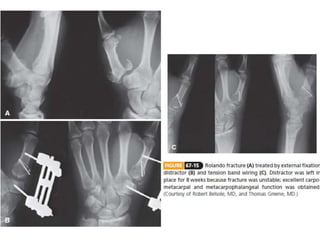

• #84 Figure 30-51 More complex fractures of the shaft can be well stabilized by (B) lateral plating. Specific care should be taken to (C) contour the plate meticulously to fit the cortex and to place the hardware in (D) the true midlateral position.